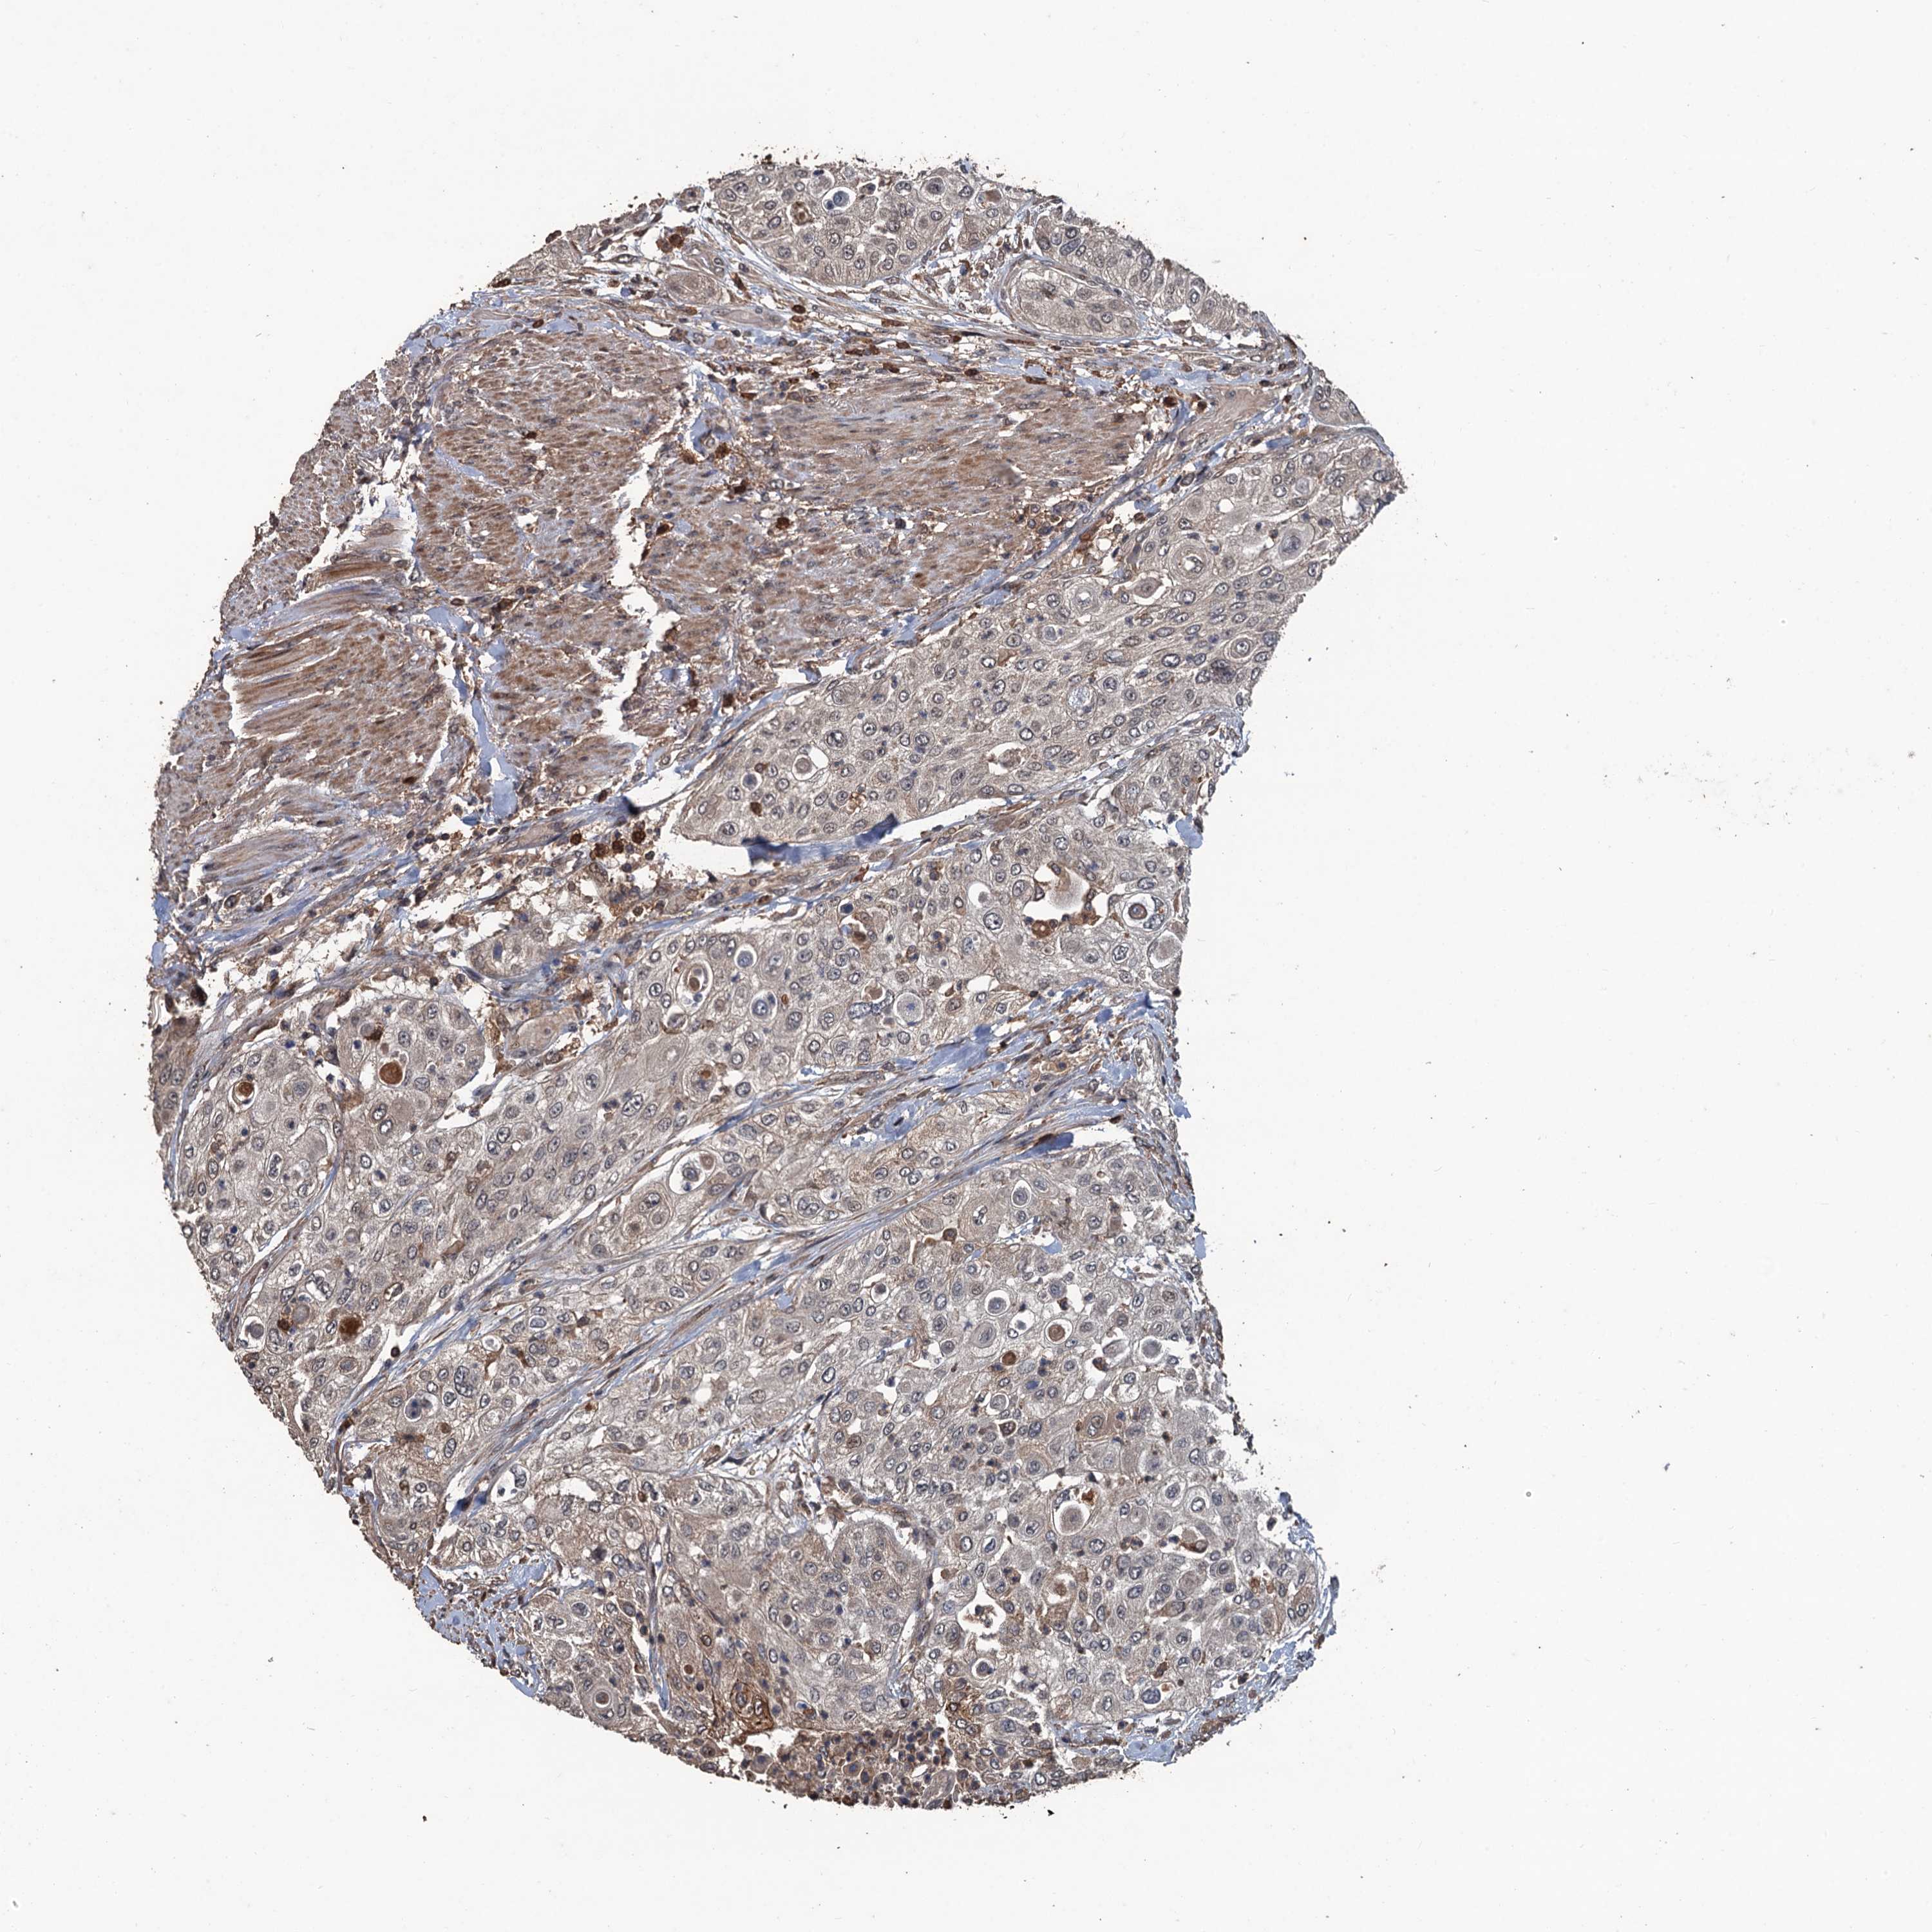

UROTHELIAL CANCER - Protein expressioni

A mouse-over function shows sample information and annotation data. Click on an image to view it in a full screen mode. Samples can be filtered based on level of antibody staining by selecting one or several of the following categories: high, medium, low and not detected. The assay and annotation is described here.

Note that samples used for immunohistochemistry by the Human Protein Atlas do not correspond to samples in the TCGA dataset.

Antibody stainingi

Antibody staining in the annotated cell types in the current human tissue is reported as not detected, low, medium, or high, based on conventional immunohistochemistry profiling in selected tissues. This score is based on the combination of the staining intensity and fraction of stained cells.

Each image is clickable and will lead to virtual microscopy that enables deeper exploration of all samples and also displays staining intensity scores, fraction scores and subcellular localization as well as patient and tissue information for each sample.

Antibody HPA039843

Staining

High

Medium

Low

Not detected

Intensity

Strong

Moderate

Weak

Negative

Quantity

>75%

75%-25%

<25%

None

Location

Nuclear

Cytoplasmic/membranous

Cytoplasmic/membranous,nuclear

Urothelial carcinoma, High grade

Urothelial carcinoma, Low grade